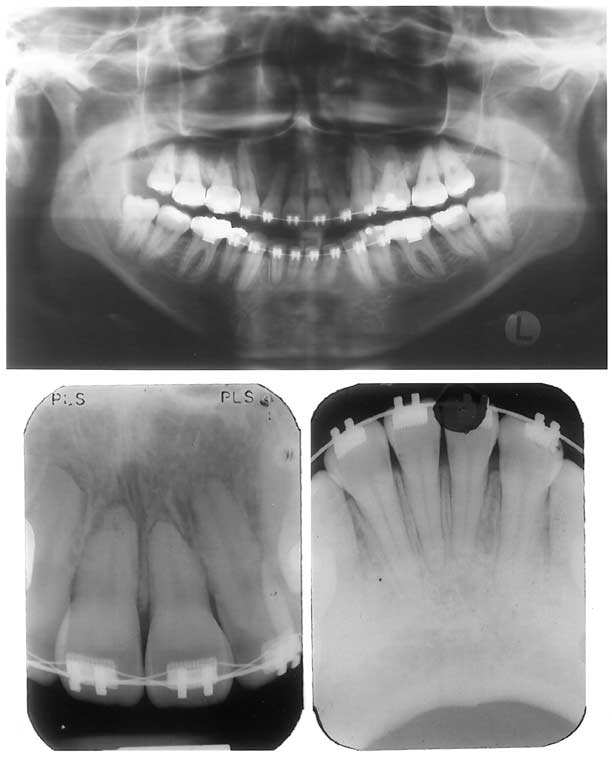

Fig 11. Posttreatment panoramic and periapical radiographs.

Note maxillary and mandibular incisors (radiographs

taken 3 months before finishing procedures,

with appliances in place).

The facial photographs show that the posttreatment profile was satisfactory (Fig 7). The patient was satisfied with her teeth and profile. The final occlusion showed reasonable Class I canine and Class II molar relationships on both sides (Figs 8-10). The maxillary third molars and the mandibular third molars were in function. Root resorption was minimal, even though this was a retreatment (Fig 11). The superimpositions show that the maxilla was slightly retruded with the extractions, and the mandible experienced a small downward and backward rotation (Fig 12 and Table). The maxillary incisors were retruded and palatally tipped even farther, and the molars moved slightly forward (Fig 12, B and C). The mandibular incisors were tipped labially and protruded, and the molars showed a slight mesial displacement and extrusion (Fig 12, D). All of these changes were expected to be associated with the treatment approach, except for the forward maxillary molar displacement. This reflects that, despite all the precautions taken, there was still some undesirable anchorage loss. This compromised attaining a perfect Class I canine relationship. Occlusal equilibration was performed after appliance removal to refine the tooth contact.